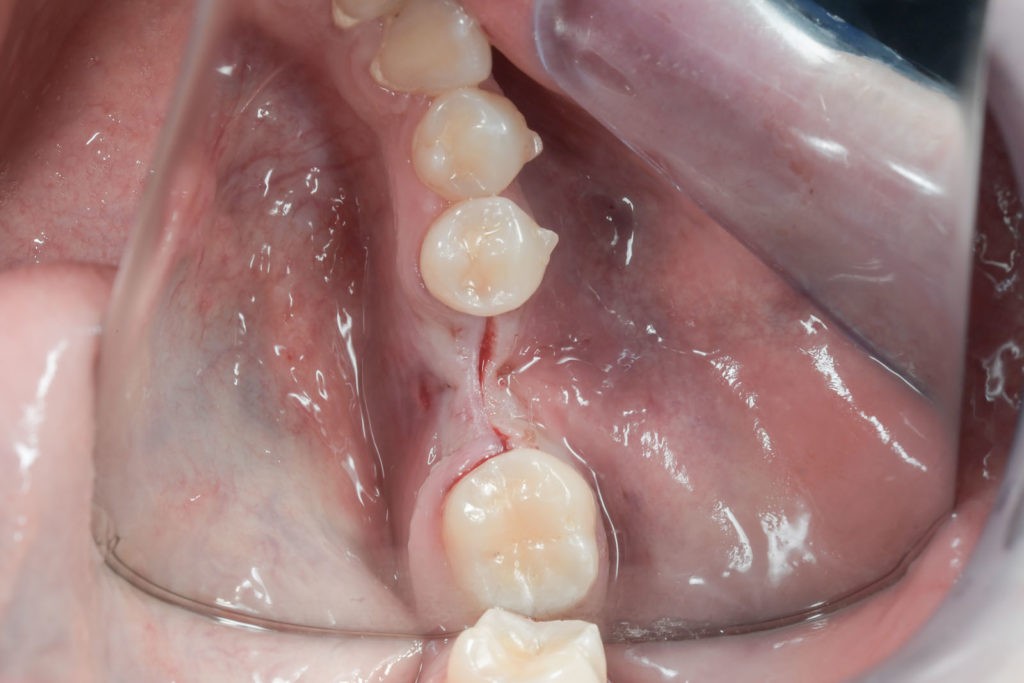

Zabieg odbudowy zębodołu powinno się wykonać możliwe jak najszybciej po usunięciu zęba. Jego celem jest odbudowa naturalnej objętości kości w miejscu utraconego zęba, a następnie szybkie wprowadzenie implantu. Najlepsze rezultaty uzyskuje się przy zastosowaniu biomateriału w formie bloczków kolagenowych lub granulatu, które dają trwałe efekty odbudowy oraz optymalną funkcję i estetykę odtworzonych koron zębów na wszczepionym implancie.

Bloki kolagenowe używane są najczęściej do odbudowy geometrycznych, trójwymiarowych ubytków kostnych, których doskonałym przykładem jest zębodół po ekstrakcji zęba. Jest to jeden ze sposobów na procedurę „socket preservation”, czyli natychmiastową lub wczesną odbudowę zębodołów poekstrakcyjnych dla osiągnięcia optymalnych efektów estetycznej odbudowy protetycznej koron zębów na implantach.